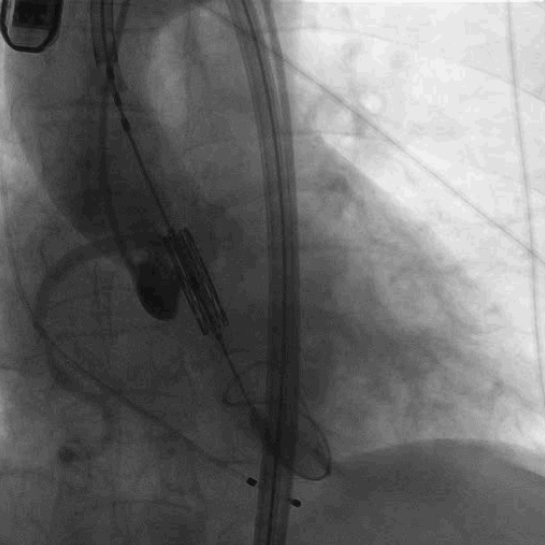

▲瓣膜释放后造影

术后,患者心率平稳,血压恢复正常,心脏造影显示患者主动脉瓣反流即刻消失,无残余瓣周漏,五天后顺利康复出院。